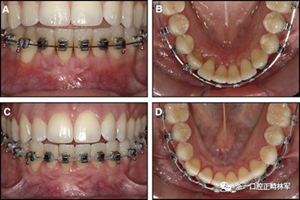

粘合保持器被移除,并放置固定裝置(圖15),僅限于患者要求的下頜弓。在第一階段牙周過程中,將結締組織移植物置于下頜右側中切牙的面?zhèn)取?個月后進行第二階段牙周過程(圖16)。包括有意識的垂直骨質評分以啟動區(qū)域加速現(xiàn)象,以及顯著的面?zhèn)群蜕鄠戎补且约m正骨開窗。隨著時間的推移,全維度弓絲及其表達的牙齒間扭矩差異顯著改善(圖17)。明智的鄰間減少之后,間隙關閉擴大接觸面,消除不美觀的黑三角。在脫粘之前也校正了牙齒排列和牙弓形態(tài)(圖18)。之前和之后的三維圖像(圖19)突出顯示在下頜右側尖牙面?zhèn)缺砻嫔瞎堑脑黾右约扒把姥栏恢玫母纳啤S捎谙骂M切牙的伸長被認為是不嚴謹?shù)?,因此輕度前牙開合沒有被矯正。

圖17.治療進展:A和B,二次手術后愈合; C和D,幾個月后牙根扭矩的改善。

圖18.脫粘后的最終圖像:A,正面視圖; B,咬合面視圖。 進一步的牙齒移動以糾正輕度前牙開合被認為不符合患者的最佳利益。

圖19.A,治療前和B,治療后的三維圖像。注意牙根位置的改善和(右下圖像)右側尖牙面?zhèn)裙琴|的形成。